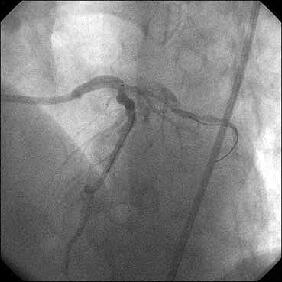

�Ǘ��72�Ώ����Brisk factor��HT, HL, DM�ł��B

��2�T�ԑO�̔��ǂƎv����Recent MI�ł��BLAD#7: total��Tristar3.0�~18?�����

�܂����B

����LCx ostium: 75%�ł��B������PCI���悤�Ǝv���̂ł����A�ǂ̂悤��strategy

���l������ł��傤���H

����ALCx take off lesion ��PCI���s���܂����B

�����搶�̌䏕����q�����ċ}篁A�a�i�����搶�j�ɗ���ŗ��Ē����܂����B

CBA(3.5?)+STENT(3.5�~13?)��strategy�ōs������ɂ��Ă��܂������A

�����ő��Z������܂����B

�ƂĂ����p���������̂ł����A�O���ɂق��̐搶��CB(3.5?)���g�p���ꂽ�̂�c��

���Ă��炸�A

�h��������3.5?�o���āI�h�ƌ�������A�h����g�������炠��܂���I�h�Ƃ���

�������Ԃ��Ă��܂����B

��������Stormer(3.5�~15?)��pre������STENT����悤�Ǝv������pre��distal����

�ɑ傫���Ă��܂��A���ǂ����̒ʂ�S670(3.5�~24?)������H�ڂɂȂĂ���

���܂����BCB�������炱��ȂɗȂ����������Ȃ��`�Ƃւ���ł��܂��܂����B

���҂���A�a�A�����Ă��������A�h�o�C�X�����������搶���A�\����܂���B

���x����͑O���ɂ������device�Ƀ`�F�b�N������悤�ɂ��܂��B

�ꉞ�A���ʂ�Y�t���܂��B